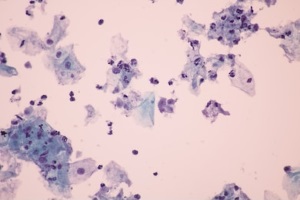

В організмі людини паразитують три види трихомонад: Trichomonas tenax, що виявляється в порожнині рота, Trichomonas hominis – у шлунково-кишковому тракті, Trichomonas vaginalis – у сечостатевому тракті. Патогенною є тільки Trichomonas vaginalis.